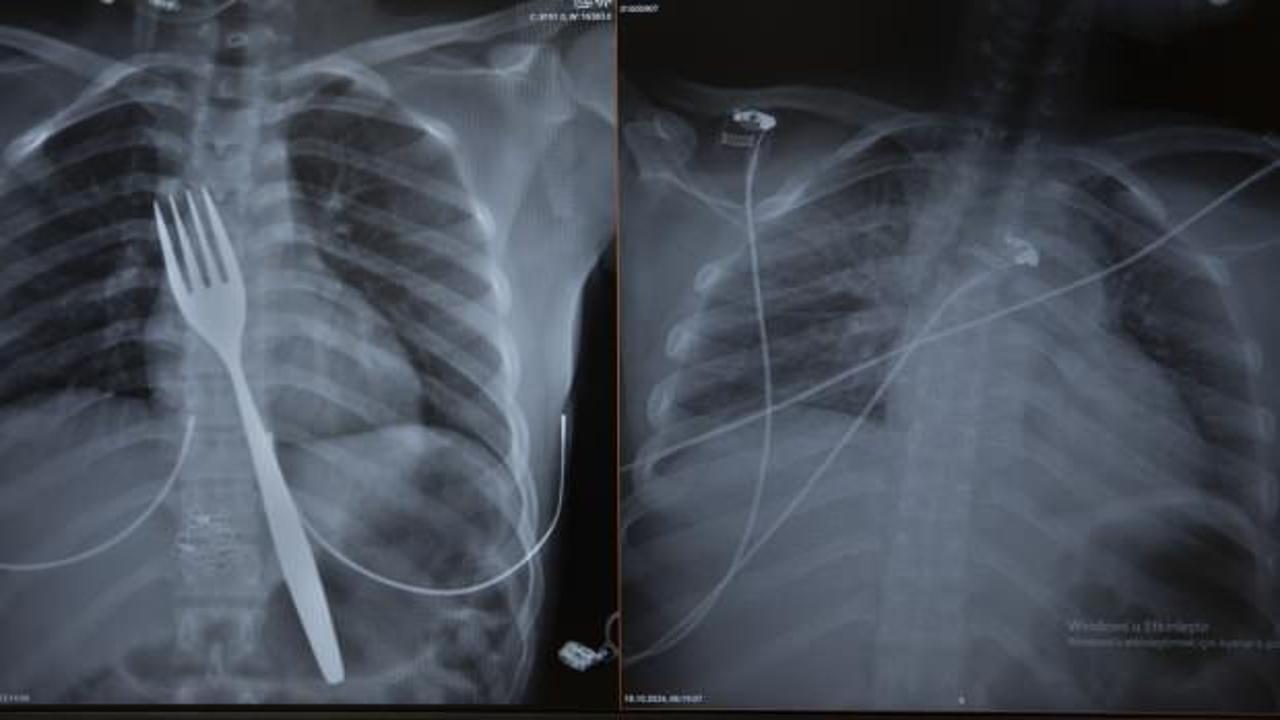

Burada röntgeni çekilen hastanın yemek borusunda 18 santimlik çatal olduğu tespit edildi.

Uzmanlar endoskopi yaparak çatalı ağızdan çıkarmayı denedi. Fakat yemek ve soluk borusuna zarar verme ihtimalinden dolayı midenin kesilerek çatalın çıkarılmasına karar verildi.

Vakayı ilk duyduğunda şaşırdığını anlatan Edizsoy, "Büyük bir çatalın tamamen yutulması şeklinde ortaya çıkan bu vakayı ilk duyduğumda doğru olmadığını düşündüm. Hasta 18 yaşında ve yabancı uyrukluydu. Türkçesi biraz zayıf olduğu için belki de yanlış anlaşılmalar olabileceğini düşündük. Ama hastanın filmini çektiğimizde gerçekten bir çatalın yemek borusunda olduğunu gördük." dedi.

"Biz en çok bu yüzden tedirgin olduk. Ama ciddi bir yaralanma olmadığını da yapılan endoskopiyle gördük. Endoskopi ile çıkarılamadı çünkü oldukça büyüktü ve endoskopik aletler için uygun değildi. Bu büyük bir yemek çatalı olduğu için kendi ağırlığı da var. Bir çivi gibi, iğne gibi tutulup çekilemiyor. Bundan dolayı karında yapılan kesi ile mideye ulaşıp midenin içinden bunu çıkarmak şeklinde bir strateji izledik. Yaptığımız bu ameliyatla da bu çatalı oradan çıkarabildik."